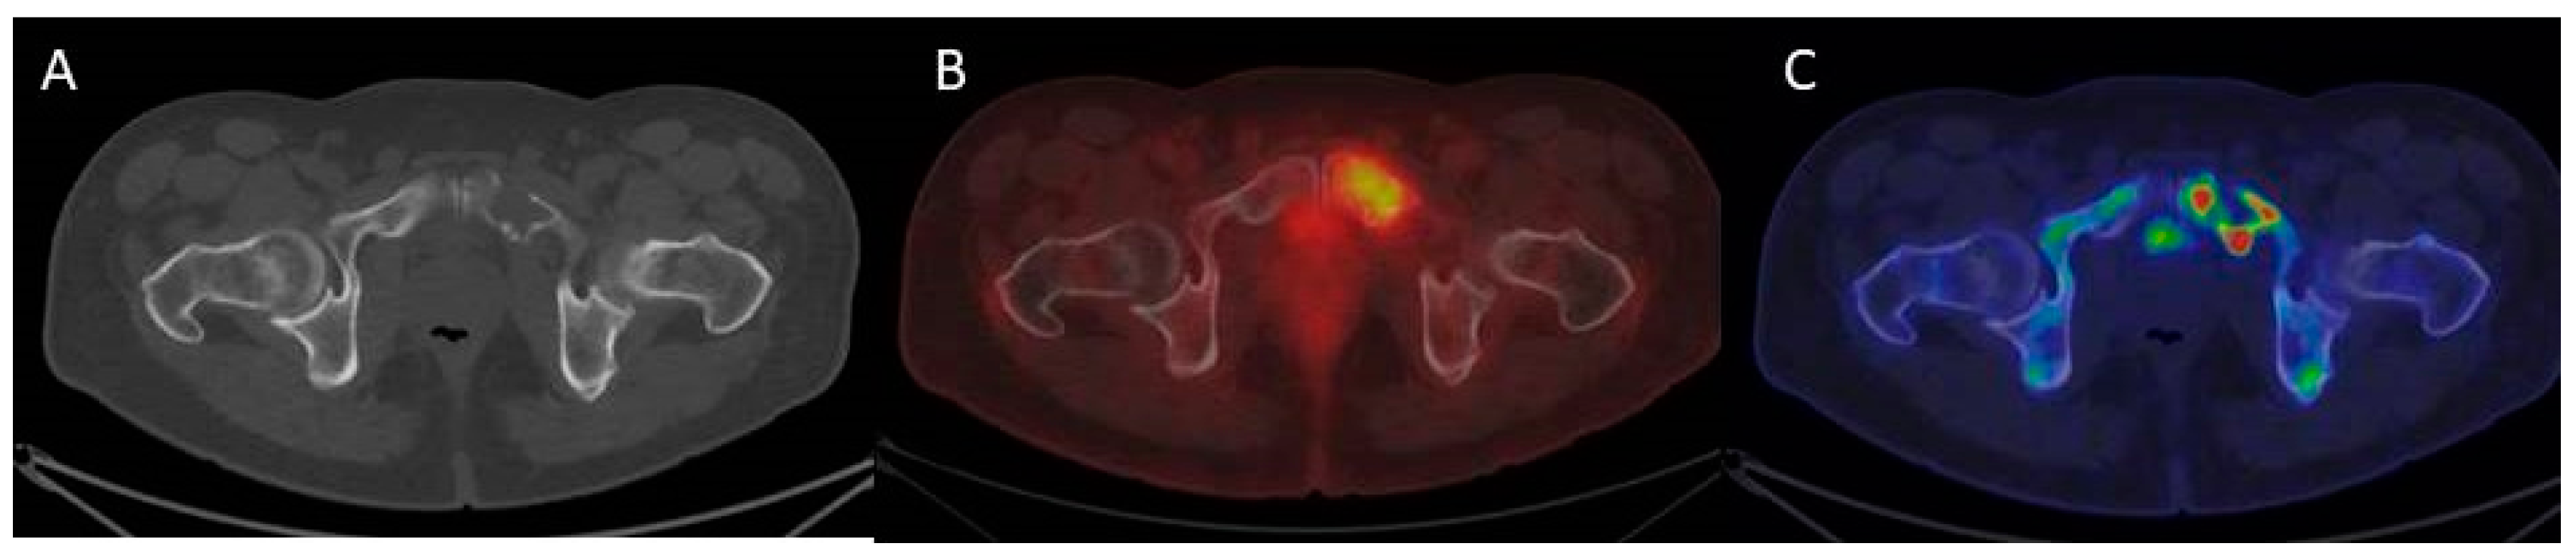

- Role of 18 F-FDG PET/CT in the Diagnosis and Management of Multiple Myeloma and Other Plasma Cell Disorders: A Consensus Statement by the International Myeloma Working Group-Clinical Key. Available online: https://www-clinicalkey-com.proxy2-bib.sdu.dk/#!/content/journal/1-s2.0-S1470204517301894 (accessed on 5 March 2020).

- Zamagni, E.; Nanni, C.; Patriarca, F.; Englaro, E.; Castellucci, P.; Geatti, O.; Tosi, P.; Tacchetti, P.; Cangini, D.; Perrone, G.; et al. A prospective comparison of 18F-fluorodeoxyglucose positron emission tomography-computed tomography, magnetic resonance imaging and whole-body planar radiographs in the assessment of bone disease in newly diagnosed multiple myeloma. Haematologica 2007, 92, 50–55. [Google Scholar] [CrossRef] [PubMed]

- Sachpekidis, C.; Goldschmidt, H.; Hose, D.; Pan, L.; Cheng, C.; Kopka, K.; Haberkorn, U.; Dimitrakopoulou-Strauss, A. PET/CT studies of multiple myeloma using (18) F-FDG and (18) F-NaF: Comparison of distribution patterns and tracers’ pharmacokinetics. Eur. J. Nucl. Med. Mol. Imaging 2014, 41, 1343–1353. [Google Scholar] [CrossRef] [PubMed]

- Ak, İ.; Onner, H.; Akay, O.M. Is there any complimentary role of F-18 NaF PET/CT in detecting of osseous involvement of multiple myeloma? A comparative study for F-18 FDG PET/CT and F-18 FDG NaF PET/CT. Ann. Hematol. 2015, 94, 1567–1575. [Google Scholar] [CrossRef] [PubMed]

- Sachpekidis, C.; Hillengass, J.; Goldschmidt, H.; Wagner, B.; Haberkorn, U.; Kopka, K.; Dimitrakopoulou-Strauss, A. Treatment response evaluation with 18F-FDG PET/CT and 18F-NaF PET/CT in multiple myeloma patients undergoing high-dose chemotherapy and autologous stem cell transplantation. Eur. J. Nucl. Med. Mol. Imaging 2017, 44, 50–62. [Google Scholar] [CrossRef] [PubMed]